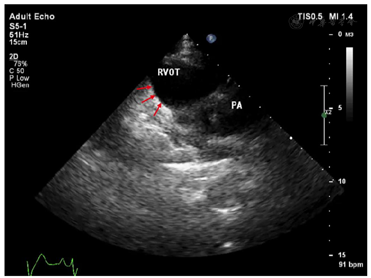

入院体格检查:体温36.4℃,脉搏70次/min,呼吸16次/min,血压110/70 mmHg(1 mmHg=0.133 kPa),神清、精神可,双侧瞳孔等大等圆,光反射灵敏,双肺呼吸音清,未及干湿啰音,心律齐,各瓣膜听诊区未闻及杂音,双下肢无水肿。心电图提示窦性心律,Brugada波Ⅱ型(图1),将V1、V2上移两个肋间复查心电图出现Brugada波穹窿型Ⅰ型(图2)。心脏超声右心室流出道远端稍增宽,右心室流出道近端内径27mm,远端内径31mm,左室功能和结构未见异常(图3)。心脏核磁显示右室心肌延迟增强,提示纤维化(图4)。冠状动脉CT血管成像(CTA)未见异常,直立倾斜试验阴性。

ARVC是由编码桥粒蛋白的基因突变引起心肌细胞间连接中断,心肌细胞坏死并被纤维脂肪组织替代。ARVC早期可单纯表现为起源于右心室的室性心律失常,晚期右心结构改变较突出,表现为右心室整体和局部扩张及功能障碍,伴明显的局部运动障碍。因此Brugada综合征与ARVC在突变基因型、有无明显的心肌病改变、心律失常的发生机制及预后方面均存在显著差异。本例患者心脏超声提示右室流出道增宽,核磁显示右室心肌纤维化,而基因检测无桥粒基因突变,心电图未发现Epsilon波,根据ARVC诊断标准(2010)专家共识的评分标准[6],本例患者尚不能诊断ARVC,但研究显示对于Brugada综合征伴有右心室结构异常的患者,发生室性心动过速风险更高,因此对于这类高危人群进一步随访尤为重要。